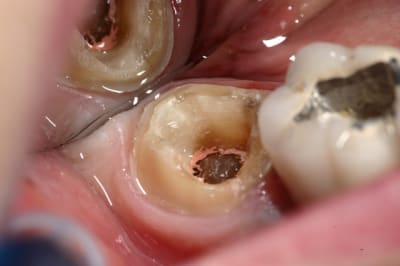

> Je ne vois pas quand un onlay n'est pas indiqué ?

> Même quand il ne reste rien, la preuve ci-dessous.